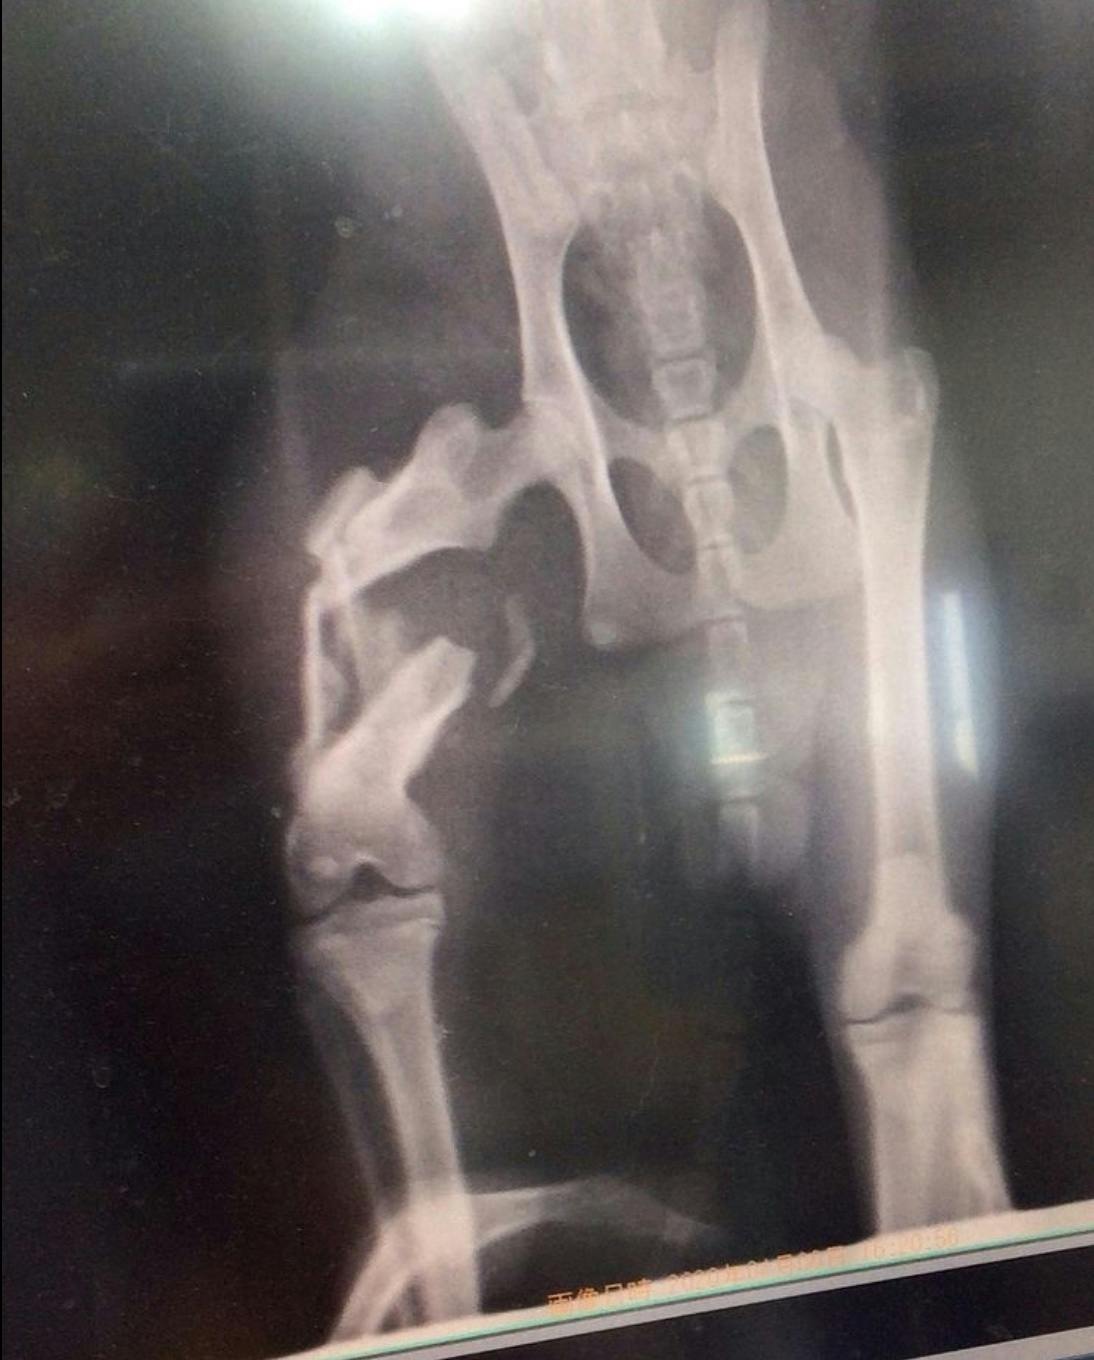

左足を骨折していて山をウロウロしているのを、町で保護され、後に保健所に送られる前に我が家に譲渡させてもらいました。

フィラリア陽性だったので2年間治療をしてきました。